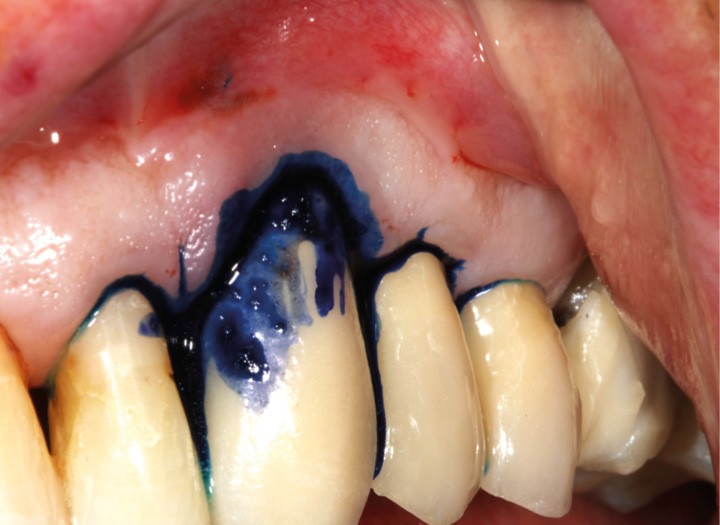

– thérapie photodynamique (bactéricide avec colorant photosensible) pour les lasers de faible énergie (600 à 800 nm),

C’est un laser idéal pour le traitement chirurgical des péri-implantites. Il permet l’élimination du tissu de granulation à la surface de l’implant et de l’os ainsi qu’une décontamination mécanique par effet photoablatif.– Le laser Diode, utilisé pour la décontamination…